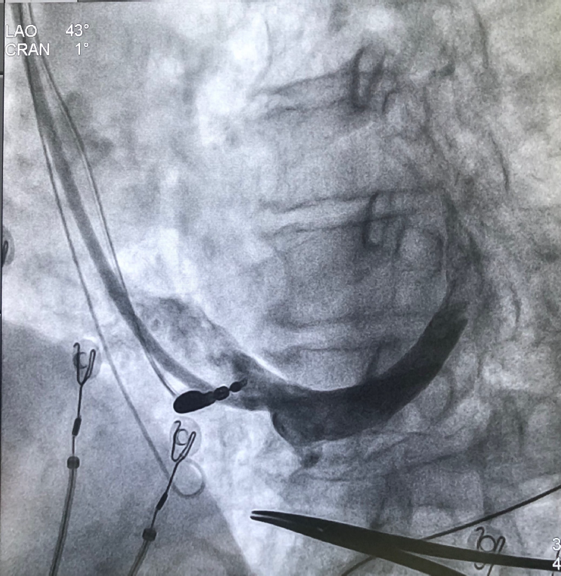

术中通过冠状窦电极将左室递送鞘置入冠状窦,用造影球囊进行造影,尝试寻找合适靶静脉放置左室电极,但造影结果发现血管光溜溜,未能发现明显侧枝静脉。尝试后退球囊在窦口附近再次造影,窦口附近疑似存在微小侧枝,但分支过于细小用PCI导丝进行尝试20分钟未能进入侧枝静脉。

由于明确患者没有合适的靶静脉,薛玉梅主任果断更换手术策略,改行左束支起搏代替左室电极,电极精准放置于左束支区域,起搏图形呈典型左束支起搏,高低电压(1V及5V)达峰时间均为75ms,确定为选择性左束支起搏。起搏阈值仅为0.7V/0.4ms,效果良好;随后心房电极及右室除颤电极均顺利植入,参数良好,在连接好机器后,完美结束手术。

术中手术过程